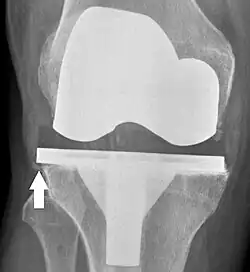

Knee replacement is routinely evaluated by X-ray, including the following measures:

- FFC: frontal femoral component angle. It is typically regarded as optimal when being 2–7° in valgus.[63]

- FTC: frontal tibial component angle, which is regarded as optimal when being at a right angle. A varus position of more than 3° has generally been found to increase the failure rate of the prosthesis.[63] -

- LTC: lateral (or sagittal) tibial component angle, which is ideally positioned so that the tibia is 0–7° flexed compared to at a right angle with the tibial plate.[63]

Loosening of the prosthesis can be indicated on X-ray by thin radiolucent spaces around the implant, or more obviously by implant displacement.[56]